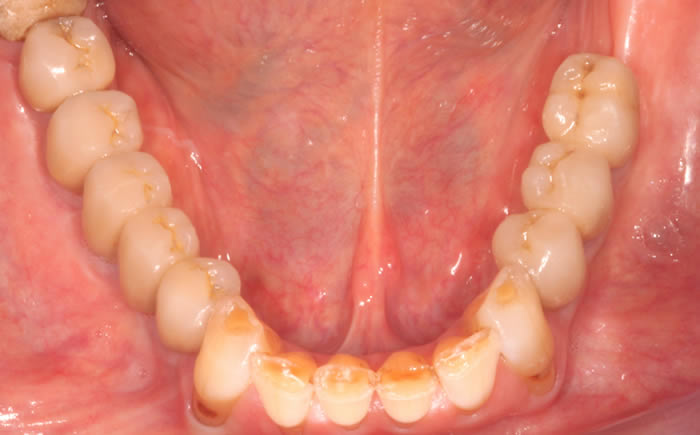

More back teeth replaced by dental implants

Case Four (4 images)